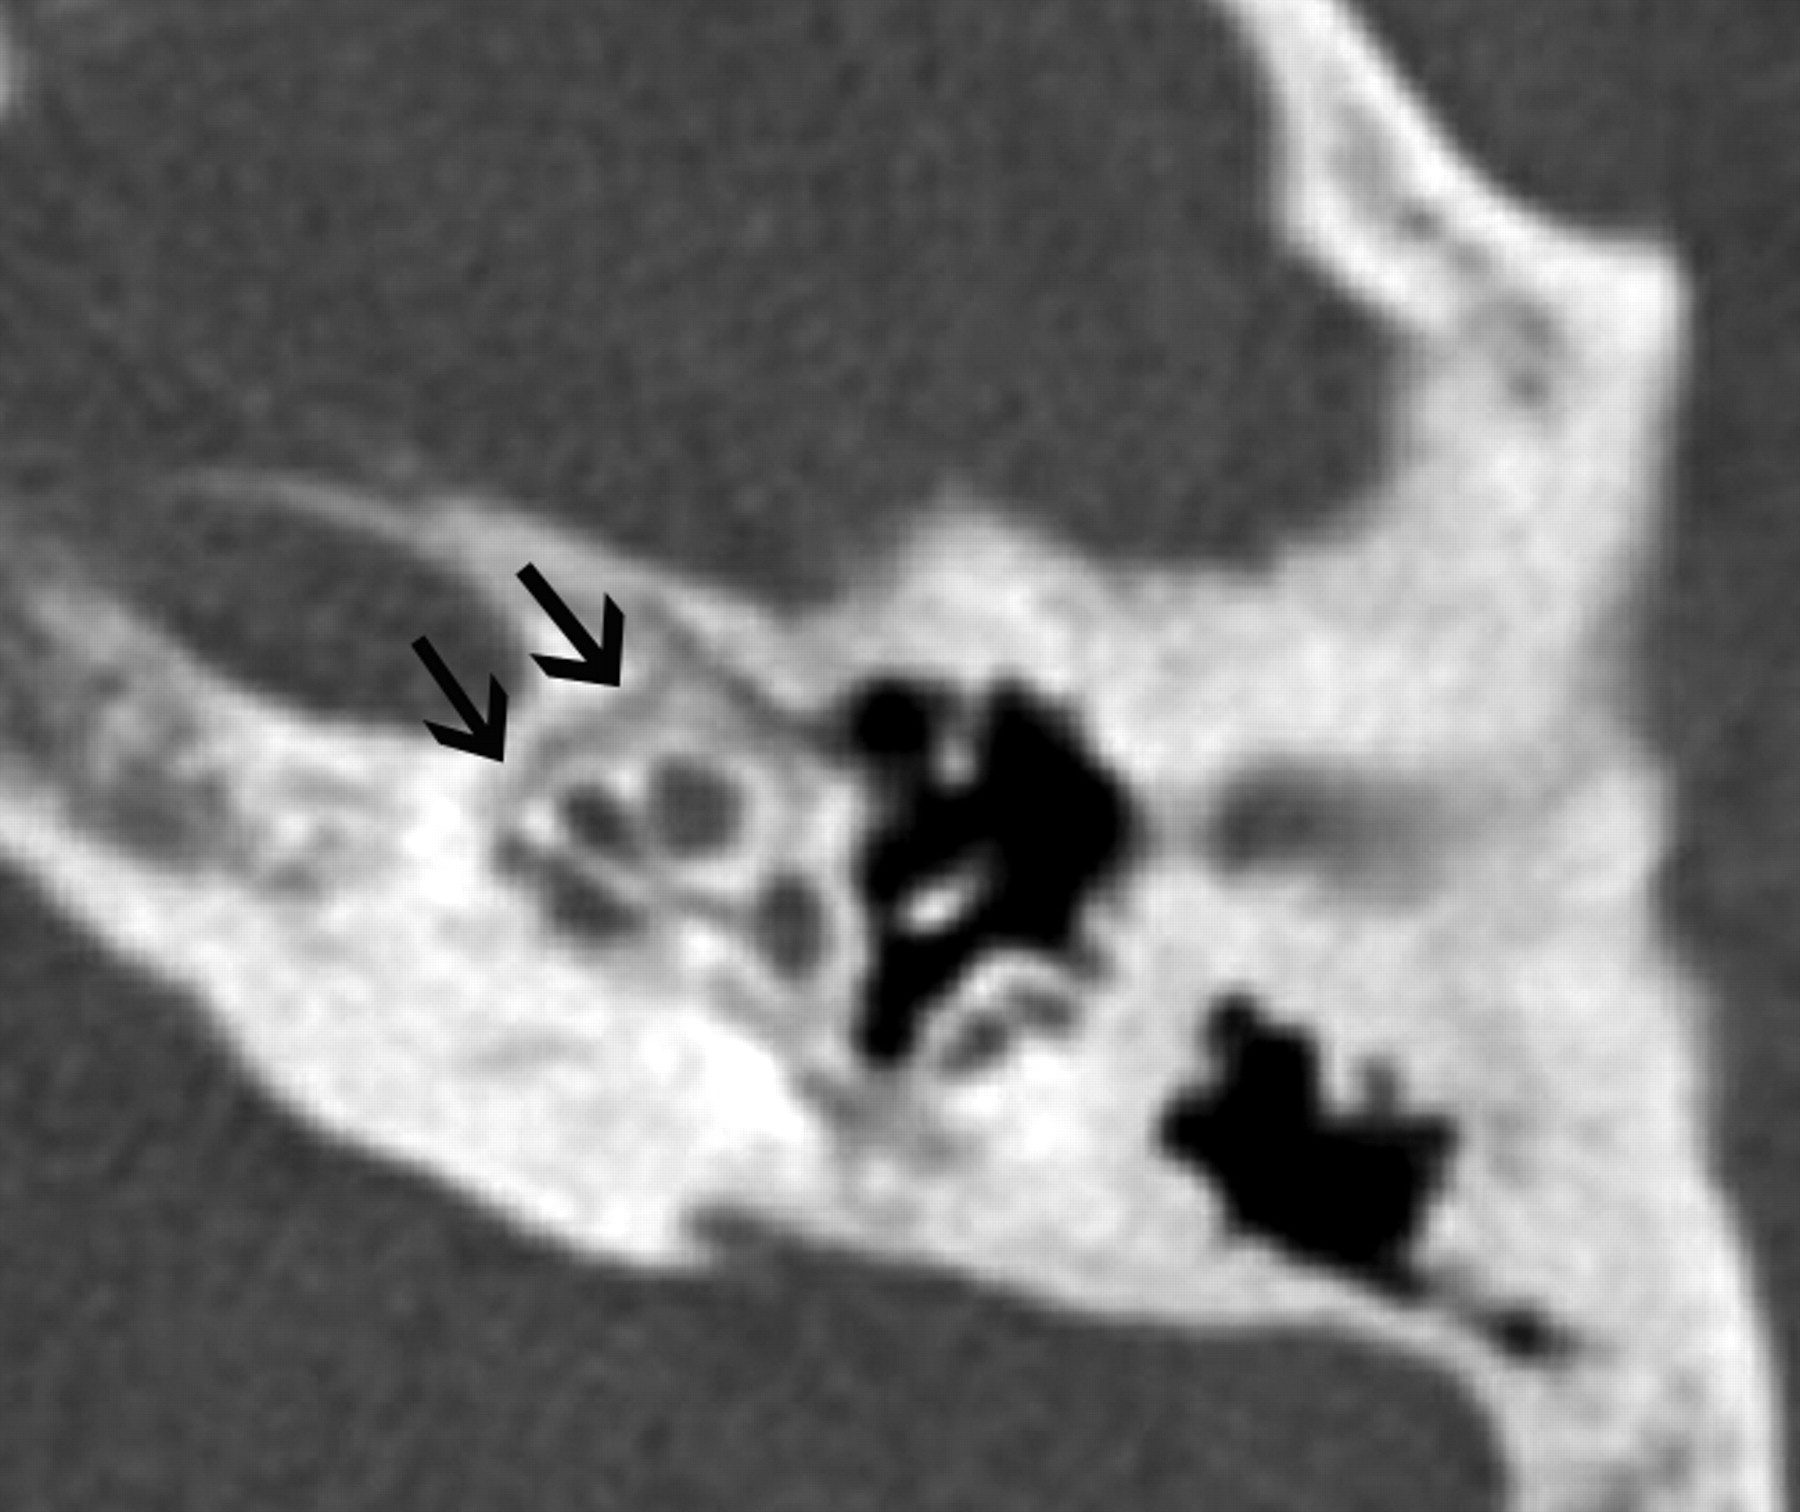

Absence of the foramen spinosum and enlargement of the proximal tympanic facial nerve canal may indicate the presence of a PSA (Fig 8A–C). The stapedial artery is normally present in the fetus but undergoes regression before birth. It arises from a normal or aberrant ICA (approximately 30% of all aberrant ICAs are associated with a PSA). The PSA typically runs through the obturator foramen (the space between the crura of the stapes) and across the promontory in the middle ear, where it can sometimes be identified. The PSA then runs along the tympanic portion of the facial nerve canal near the geniculate fossa, finally exiting the facial nerve canal to enter the middle cranial fossa to become the middle meningeal artery.

A 30-year-old man with PSA. A, Axial CT image demonstrates absence of the foramen spinosum bilaterally (black arrows). B, Coronal CT image in the same patient shows enlargement of the tympanic part of the facial nerve canal, another indirect imaging sign of PSA. C, Lateral DSA image of the internal carotid injection shows the PSA arising from the ICA (arrows).

When the stapedial artery persists beyond the fetal period, the middle meningeal artery does not develop from the internal maxillary artery and the foramen spinosum remains undeveloped. The absence of the foramen spinosum is an important CT finding that should alert the radiologist to a possible PSA (Fig 8A). However, these findings do need to be interpreted cautiously because the foramen spinosum may be absent in ≤3% of all skull base CT studies.35 The presence of additional signs such as a subtle enlargement of the tympanic segment of the ipsilateral facial nerve canal on coronal CT images, just inferior to the lateral semicircular canal, may raise the index of suspicion (Fig 8B), and DSA can be used for confirmation (Fig 8C). Most patients with a PSA remain asymptomatic and only rarely present with pulsatile tinnitus. The physical examination in some patients may show a red retrotympanic mass, which may provide useful clinical correlation for the imaging findings.